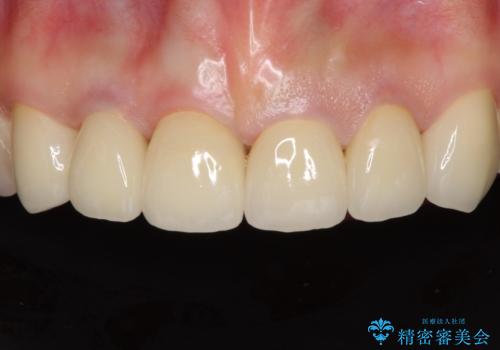

クロスバイト改善中には歯髄壊死を起こすリスクがあるため、神経に問題がないか確認しながら治療を進めて行く必要があります。

思っていたよりも早くクロスバイトは改善され、歯髄壊死に至ることなく、無事に治療を終えることができました。